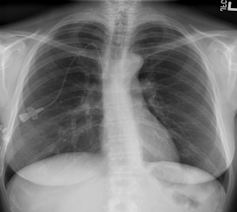

Se recurre a esta técnica de imagen porque, debido a la afectación primaria del sistema respiratorio, la infección por SARS-CoV-2 deja evidencias radiológicas de neumonía visibles bajo los rayos X. Concretamente, la neumonía asociada a la covid-19 produce sombras en los pulmones conocidas como opacidad de vidrio esmerilado. Estas opacidades suelen aparecer con una distribución periférica o posterior, principalmente en los lóbulos inferiores y con menos frecuencia en el lóbulo medio derecho.

En los dos primeros días de la infección, el 50% de los pacientes de covid-19 ya muestra lesiones pulmonares parenquimatosas, superando el 90% entre los 3 y 5 días. Lo sorprendente es que esto ocurre incluso en pacientes asintomáticos. Por ello, complementar la RT-PCR con una radiografía de tórax mejora la sensibilidad en el diagnóstico, reduciendo significativamente el número de falsos negativos. Es importante porque los falsos negativos son precisamente el talón de Aquiles de la prueba RT-PCR, cuya sensibilidad oscila entre el 70-90%. Otra ventaja importante es que la radiografía está lista en cuestión de minutos.

La única pega al uso de esta técnica es que su despliegue masivo tiene un significativo cuello de botella: la necesidad de radiólogos expertos para interpretar y analizar las imágenes. Adicionalmente, el análisis individual de la radiografía de tórax, tal y como lo conocemos, también adolece de una baja sensibilidad, lo que sugiere la necesidad de herramientas complementarias de análisis computerizado.